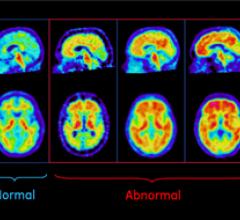

GE Healthcare showcased at the Radiological Society of North America Annual Meeting (RSNA 2013) a work-in-progress product for positron emission tomography (PET) that quickly and confidently evaluates a patient’s response to cancer treatment.